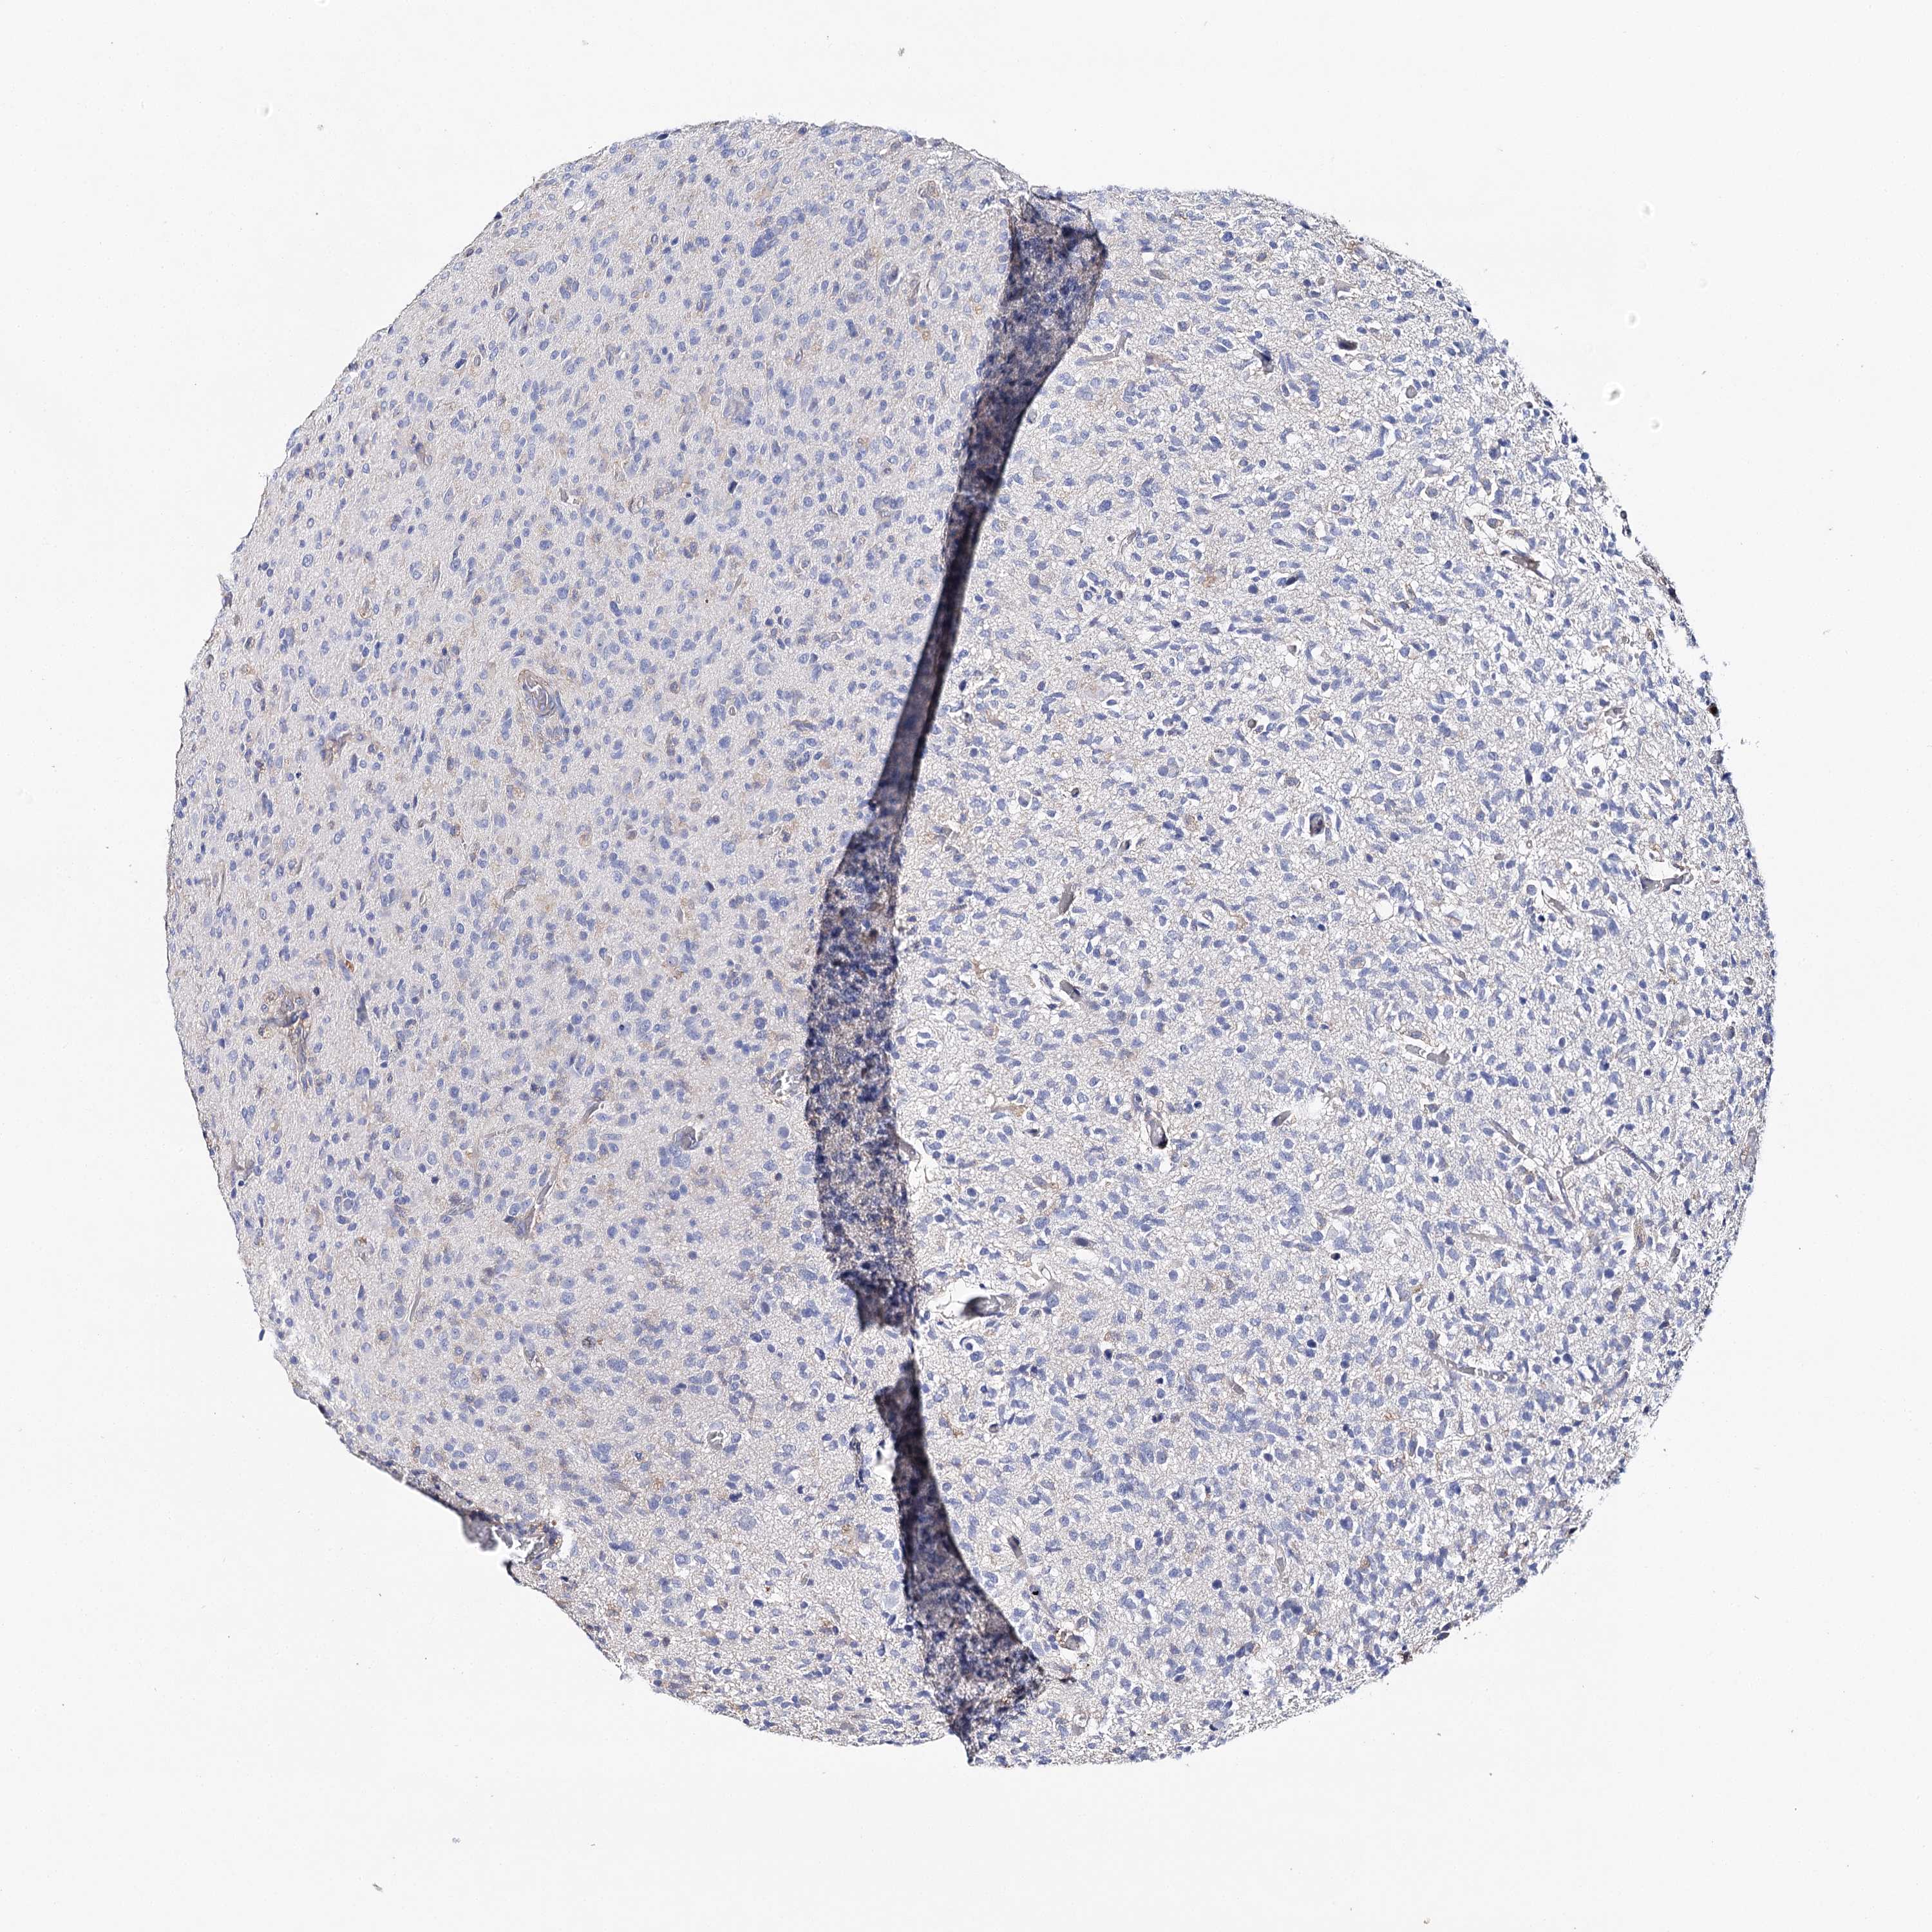

GLIOMA - Protein expressioni

A mouse-over function shows sample information and annotation data. Click on an image to view it in a full screen mode. Samples can be filtered based on level of antibody staining by selecting one or several of the following categories: high, medium, low and not detected. The assay and annotation is described here.

Note that samples used for immunohistochemistry by the Human Protein Atlas do not correspond to samples in the TCGA dataset.

Antibody stainingi

Antibody staining in the annotated cell types in the current human tissue is reported as not detected, low, medium, or high, based on conventional immunohistochemistry profiling in selected tissues. This score is based on the combination of the staining intensity and fraction of stained cells.

Each image is clickable and will lead to virtual microscopy that enables deeper exploration of all samples and also displays staining intensity scores, fraction scores and subcellular localization as well as patient and tissue information for each sample.

Antibody HPA038212

Antibody HPA045455

Glioma, malignant, High grade

Glioma, malignant, Low grade

Glioblastoma, NOS